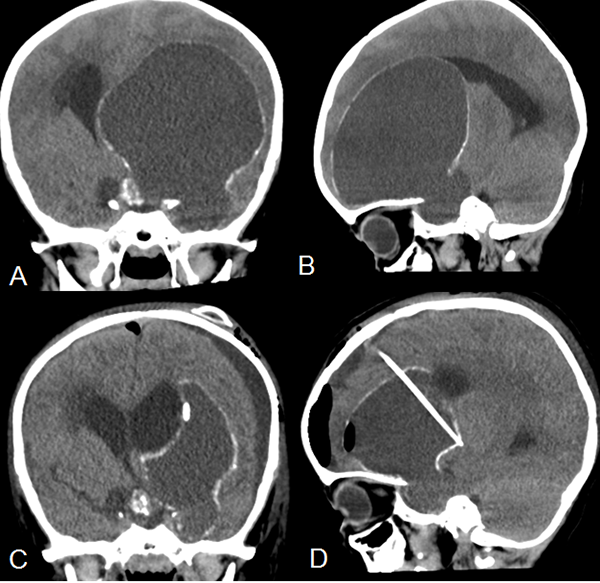

El tratamiento de los craneofaringiomas continúa planteando una controversia a lo largo del mundo.13La exéresis quirúrgica completa es el tratamiento ideal ya que permite mejor control de la enfermedad.14-16 Sin embargo, debido a la ubicación en la región selar y sus relaciones (el amplio contacto con el quiasma, el eje hipotálamo-hipofisario y las arterias del polígono de Willis), la exéresis completa sin producir daños a las estructuras circundantes es difícil de conseguir (figura 1).17-22

Figura 1. Resonancia magnética de cerebro con contraste. A y B. Corte sagital y coronal respectivamente donde se observa tumor sólido quístico en la región selar supraselar compatible con craneofaringioma.